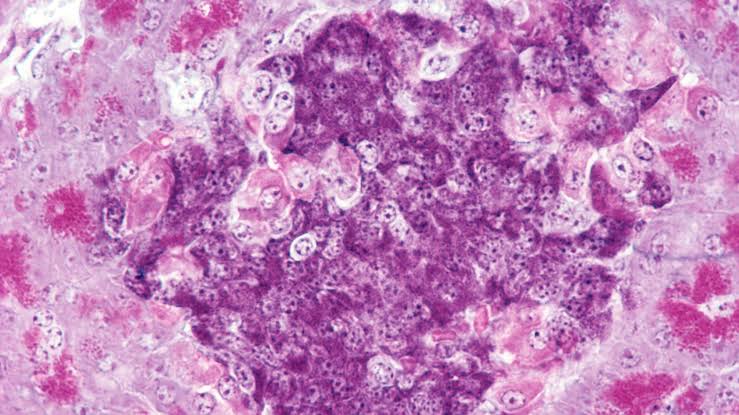

By creating a hybrid immune system between the host and the donor, researchers were able to transplant insulin-producing cells that were not rejected.